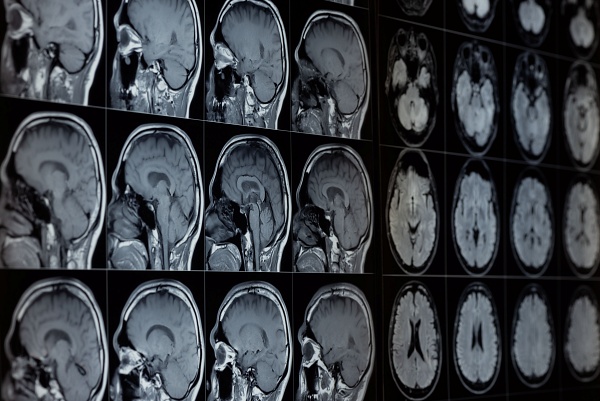

[디지털투데이 AI리포터] 중국과 미국을 중심으로 인공지능(AI)이 의료 현장에서 빠르게 활용 범위를 넓히고 있다. 암 조기 진단부터 병원 운영 효율화까지 성과가 이어지는 한편, 임상적 한계와 윤리적 우려도 동시에 제기된다.7일(현지시간) 온라인 매체 기가진에 따르면, 중국에서는 알리바바 산하 다모 아카데미(Damo Academy)가 개발한 AI 툴 'PANDA'(PANcreatic cancer Detection with Artificial intelligence)를 활용한 췌장암 조기 발견 실험이 진행 중이다. PANDA는 조영제...